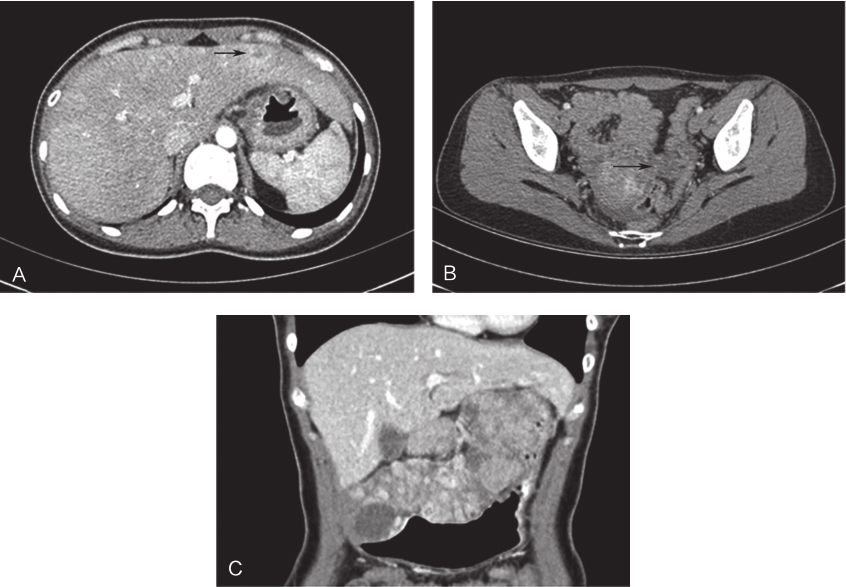

患者术后7天恢复出院。患者出院诊断为:野生型(胃)胃肠间质瘤伴肝脏及淋巴结多发转移。2017年行病例筛查时MDT团队分析认为其符合SDH(-)表现,行免疫组织化学染色示:SDH(-),结合指南变更给予舒尼替尼(索坦)靶向治疗,37.5mg/d。截至2018年6月,随访25个月(图8),患者无明显不良反应,肝脏转移病灶完全缓解,其余部位未发现明显复发转移迹象。

图8术后25个月复查CT